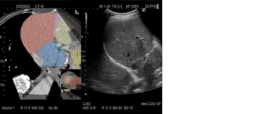

(3)Real-time Virtual Sonography(RVS)

RVSは、超音波画像と他モダリティ画像をリアルタイムに並列表示する機能である。超音波検査だけでは発見しづらい小さな病変の発見や、治療部位の決定など安全かつ正確な治療への貢献が期待される。「ARIETTA 850 DeepInsight x」「ARIETTA 750 DeepInsight x」は、RVSによる検査開始時のボリュームデータ検索や、バーチャル像と超音波画像との位置合わせを自動化し、操作手順を低減した。検査者の習熟度を問わず簡単に使用することが可能で、検査の短時間化も期待できる。

また、CT/MR画像などのバーチャル像の情報から領域を分類して超音波(US)画像に重ねて表示することが可能である。これにより、描出部位の位置関係をわかりやすく可視化し、検査をスムーズに進めるとともに、ワークフローの効率化によって検査時間の短縮が期待される。